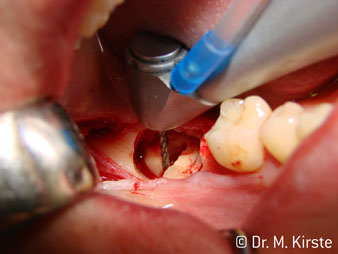

Die professionelle Lagergestaltung im Innenleben des Handstückkopfes garantiert einen ruhigen Lauf der Bohrer, bei der Zahn- oder Wurzelseparation (Abb. 4 - 9) zeigt sich ein beeindruckendes Schnittbild ohne Schlageffekte.

Abb. 4